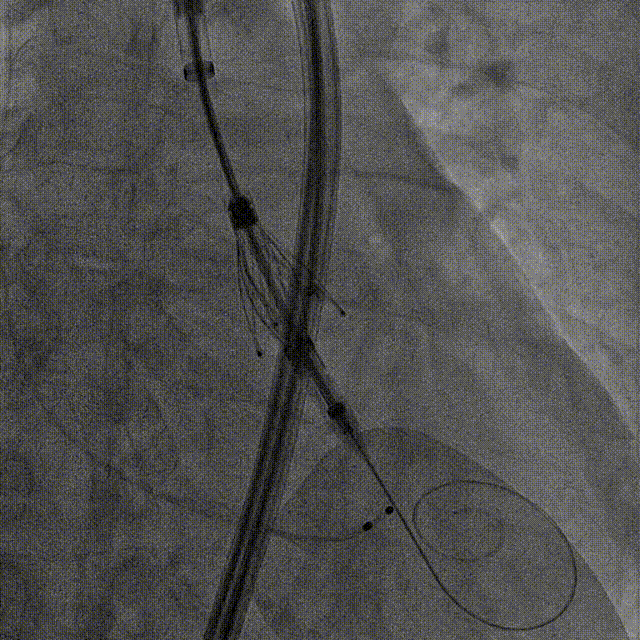

Case 4

重度反流心衰伴冠脉多支病变

(EF37%)

手术过程:5A 标准化流程SOP

左冠造影

小右冠,弥漫性病变

LAD术后造影

根部造影

长鞘植入

输送器定位

右窦中心对齐

定位键窦对齐

无窦确认

右窦观察

左窦确认

深度确认

一键脱钩

术后造影